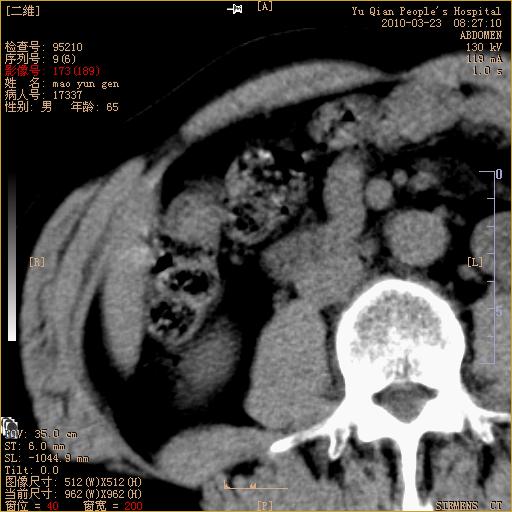

标题: CT25266:消瘦月余,前来肝部检查,请看看肠腔 [打印本页]

标题: CT25266:消瘦月余,前来肝部检查,请看看肠腔

肝区结肠占位,腺癌可考虑,建议肠镜活检。

升结肠肠壁增厚,不均强化,考虑升结肠腺癌可能性,建议肠镜检查。

1)考虑升结肠癌。2)右肾小囊肿。